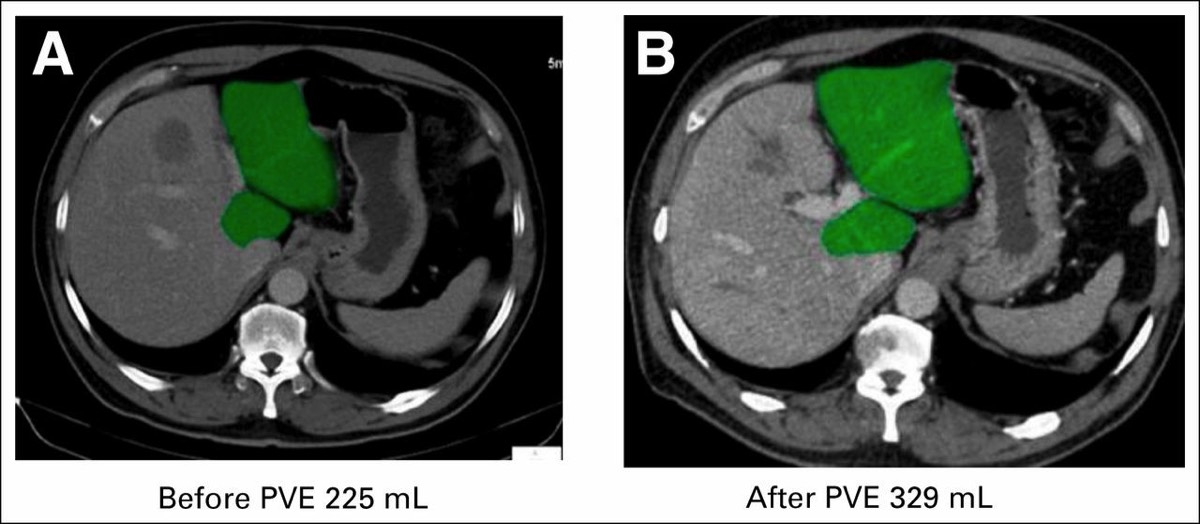

As liver, pancreas and biliary surgery push into new frontiers, so does the technology needed to plan these complex procedures. Whether laparoscopic or open surgery, every possible detail of the patient's care is analyzed to ensure surgery is safe and effective. 3D reconstructed imaging is used to plan surgery. No aspect of patient care is taken for granted.